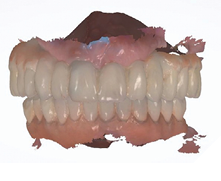

The patient returned 2 weeks from the impressioning appointment for a prototype try in. At this appointment the esthetics, phonetics, soft tissue approximation and occlusion were confirmed. There was no requirement for a verification jig due to the accuracy of the Nexus solution. The restorations were manufactured with milled gold anodized titanium bars overlaid with monolithic zirconia (Figs. 24A-C, 25A-C).

Fig. 24A

Fig. 24B

Fig. 24C